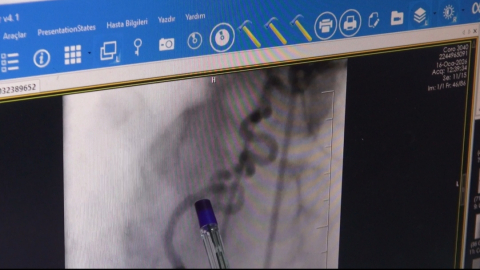

Medipol Koşuyolu Hastanesi Kardiyoloji Uzmanı Prof. Dr. Zekeriya Nurkalem, ağız sağlığının hafife alınmaması gerektiği konusunda uyarılarda bulundu. Tıpta ‘periodontitis’ olarak bilinen diş eti iltihabının sadece ağızla sınırlı kalmadığını belirten Prof. Dr. Nurkalem, ‘Bu durum damar duvarlarında plak oluşumunu tetikleyerek kalp krizi ve ritim bozukluklarına doğrudan yol açabilir’ diye konuştu.

Prof. Dr. Nurkalem, diş eti iltihabının fibrinojen gibi pıhtılaşma faktörlerini artırarak damar içi pıhtı oluşumuna zemin hazırladığını vurguladı. Ayrıca kalp pili ve diğer yabancı materyallerin iltihaplanmasının endokardit gibi kalp zarında iltihaplanmalara yol açabileceğini belirtti. Prof. Dr. Nurkalem, “Diş eti iltihabı, atrial fibrilasyon gibi ritim problemlerini de tetikleyebilir. Bu ritim bozuklukları kalp içinde pıhtı oluşumu ve inme riskini artırır” dedi.

Kalp sağlığını korumanın diş sağlığından geçtiğine dikkat çeken Prof. Dr. Nurkalem, “Günde en az bir kez dişlerinizi fırçalamak riskinizi ciddi şekilde azaltır. Diş kontrollerinizi ihmal etmeyin. Eğer diş eti iltihabınız varsa kalp kontrollerinizi de yaptırmanız önemli” ifadelerini kullandı. Prof. Dr. Nurkalem, kalp ameliyatlarında alınan dokularda yapılan testlerde diş eti patojenlerine sıkça rastlandığını ve bu durumun iki sağlık sorunu arasındaki doğrudan ilişkiyi ortaya koyduğunu belirtti.